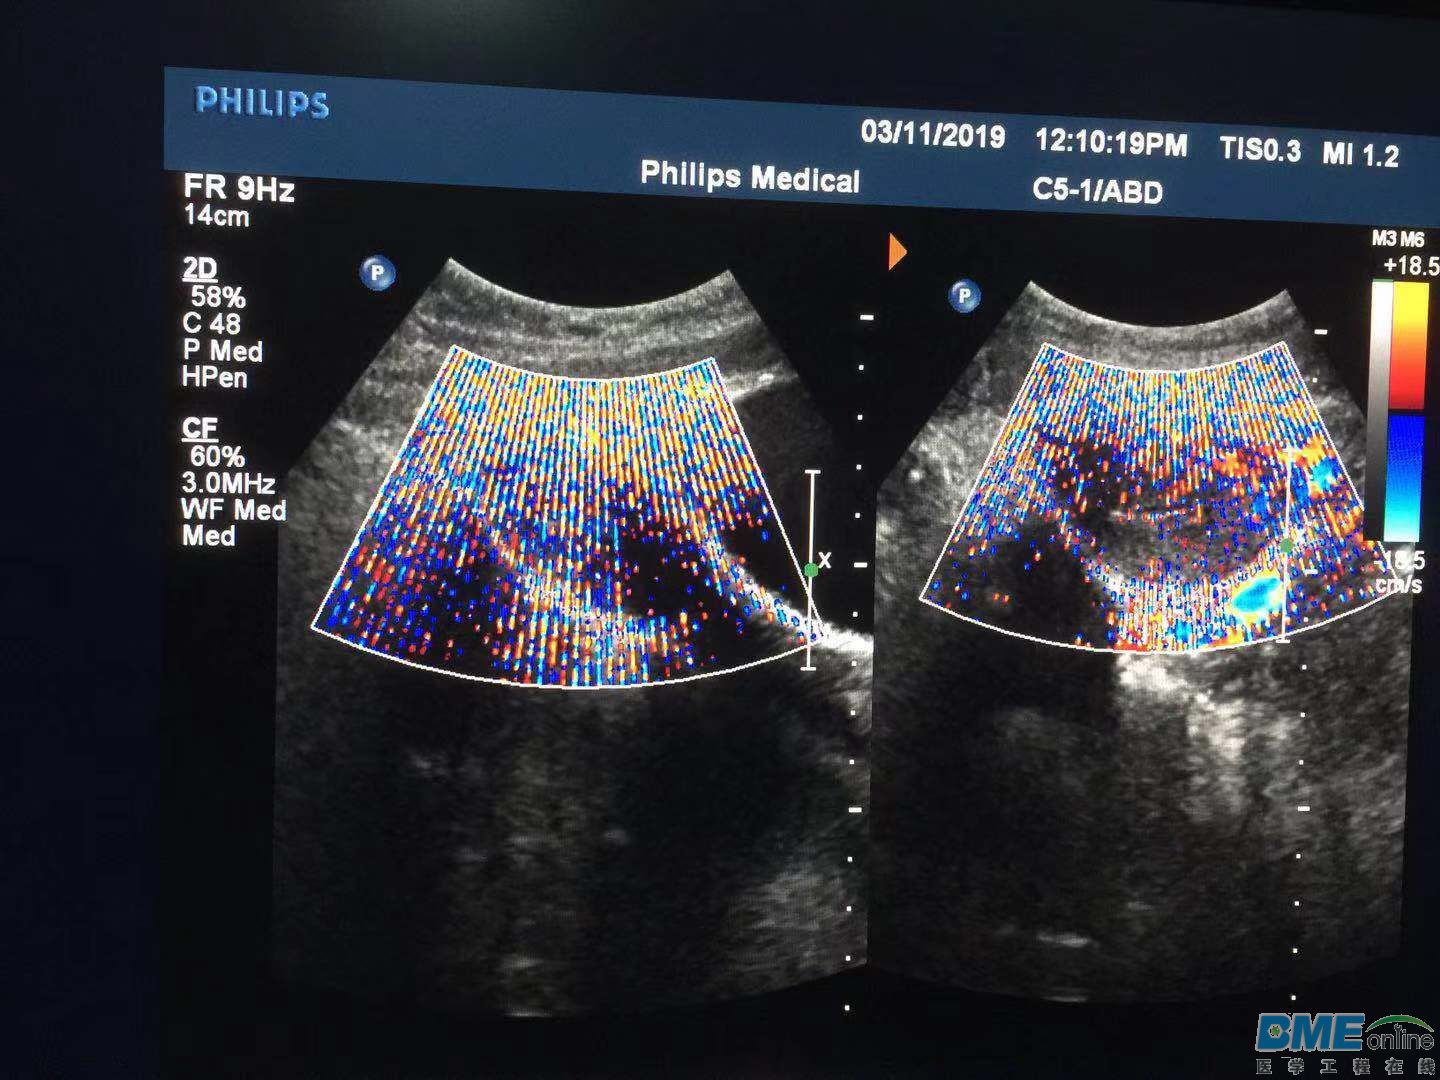

[设备故障求助] 飞利浦开机一两小时后出现这现象,打开后面机箱盖子过会正常。求教什么地方出现问题

微信图片_20190311173139.jpg 微信图片_20190311173133.jpg 微信图片_20190311173145.jpg

具体什么机型?二维图像正常吗?

IE33二维正常

我之前遇到过类似问题,扫血流的时候就会出现这种情况,后来我把工作站视频线取下来,故障就消除了,发现是接地问题,然后重新把接地线处理了一下